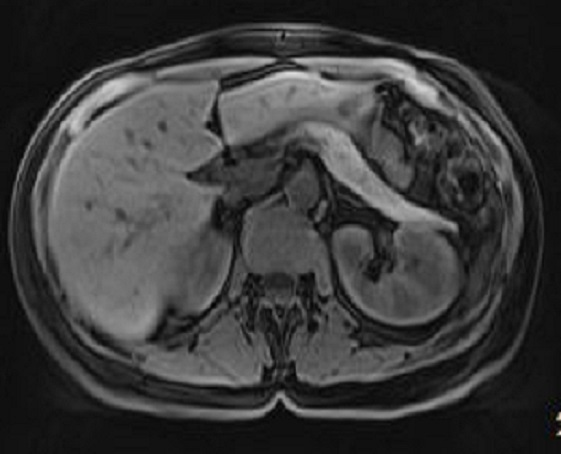

Les images de IRM en

ponderation T1 sont fondamentation de explore le

pancreas . Sur les sequences de saturation de

graisse ( FAT SAT ) le pancreas est hyperintense que

les autres organes de l'abdomen ( voie image)

Image IRM en coupe axiale en ponderation

sur T2 : La vesicule biliaire et des voies biliaire

intrahepatique est tres hyperintense .

Le pancreas est moin intense que la rate |